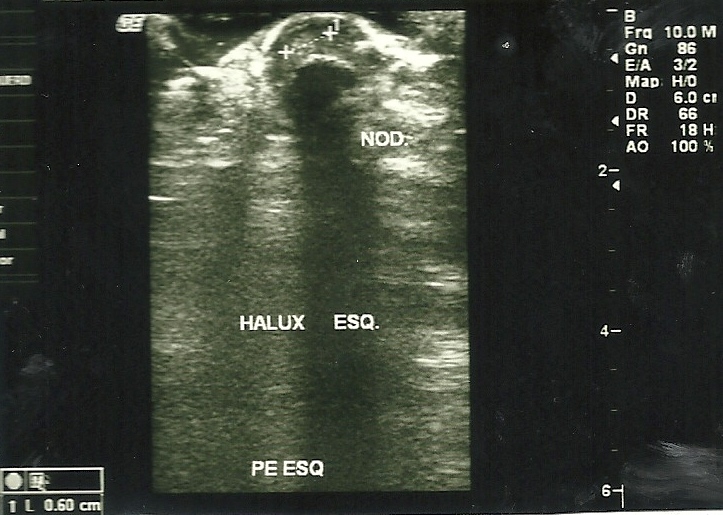

Relatamos um caso de mulher, 51 anos, com história de longa duração de alterações no aspecto da unha do hálux esquerdo e dor local intensa. Após diversos tratamentos, já com o diagnóstico de verruga subungueal, foi suspeitada a existência de tumor glômico pela história clínica e testes semiológicos sugestivos. Foi realizada cirurgia, com a confirmação histopatológica das duas hipóteses.

O possível diagnóstico é a soma de história clínica sugestiva, testes ambulatoriais e exames de imagem, contudo somente confirmado pela histopatologia.